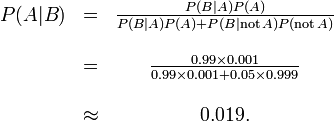

False positives in a medical test

False positives result when a test falsely or incorrectly reports a positive result. For example, a medical test for a disease may return a positive result indicating that patient has a disease even if the patient does not have the disease. We can use Bayes' theorem to determine the probability that a positive result is in fact a false positive. We find that if a disease is rare, then the majority of positive results may be false positives, even if the test is accurate.

Suppose that a test for a disease generates the following results:

- If a tested patient has the disease, the test returns a positive result 99% of the time, or with probability 0.99

- If a tested patient does not have the disease, the test returns a positive result 5% of the time, or with probability 0.05.

Naively, one might think that only 5% of positive test results are false, but that is quite wrong, as we shall see.

Suppose that only 0.1% of the population has that disease, so that a randomly selected patient has a 0.001 prior probability of having the disease.

We can use Bayes' theorem to calculate the probability that a positive test result is a false positive.

Let A represent the condition in which the patient has the disease, and B represent the evidence of a positive test result. Then, probability that the patient actually has the disease given the positive test result is

and hence the probability that a positive result is a false positive is about  , or 98%.

, or 98%.

Despite the apparent high accuracy of the test, the incidence of the disease is so low that the vast majority of patients who test positive do not have the disease. Nonetheless, the fraction of patients who test positive who do have the disease (.019) is 19 times the fraction of people who have not yet taken the test who have the disease (.001). Thus the test is not useless, and re-testing may improve the reliability of the result.